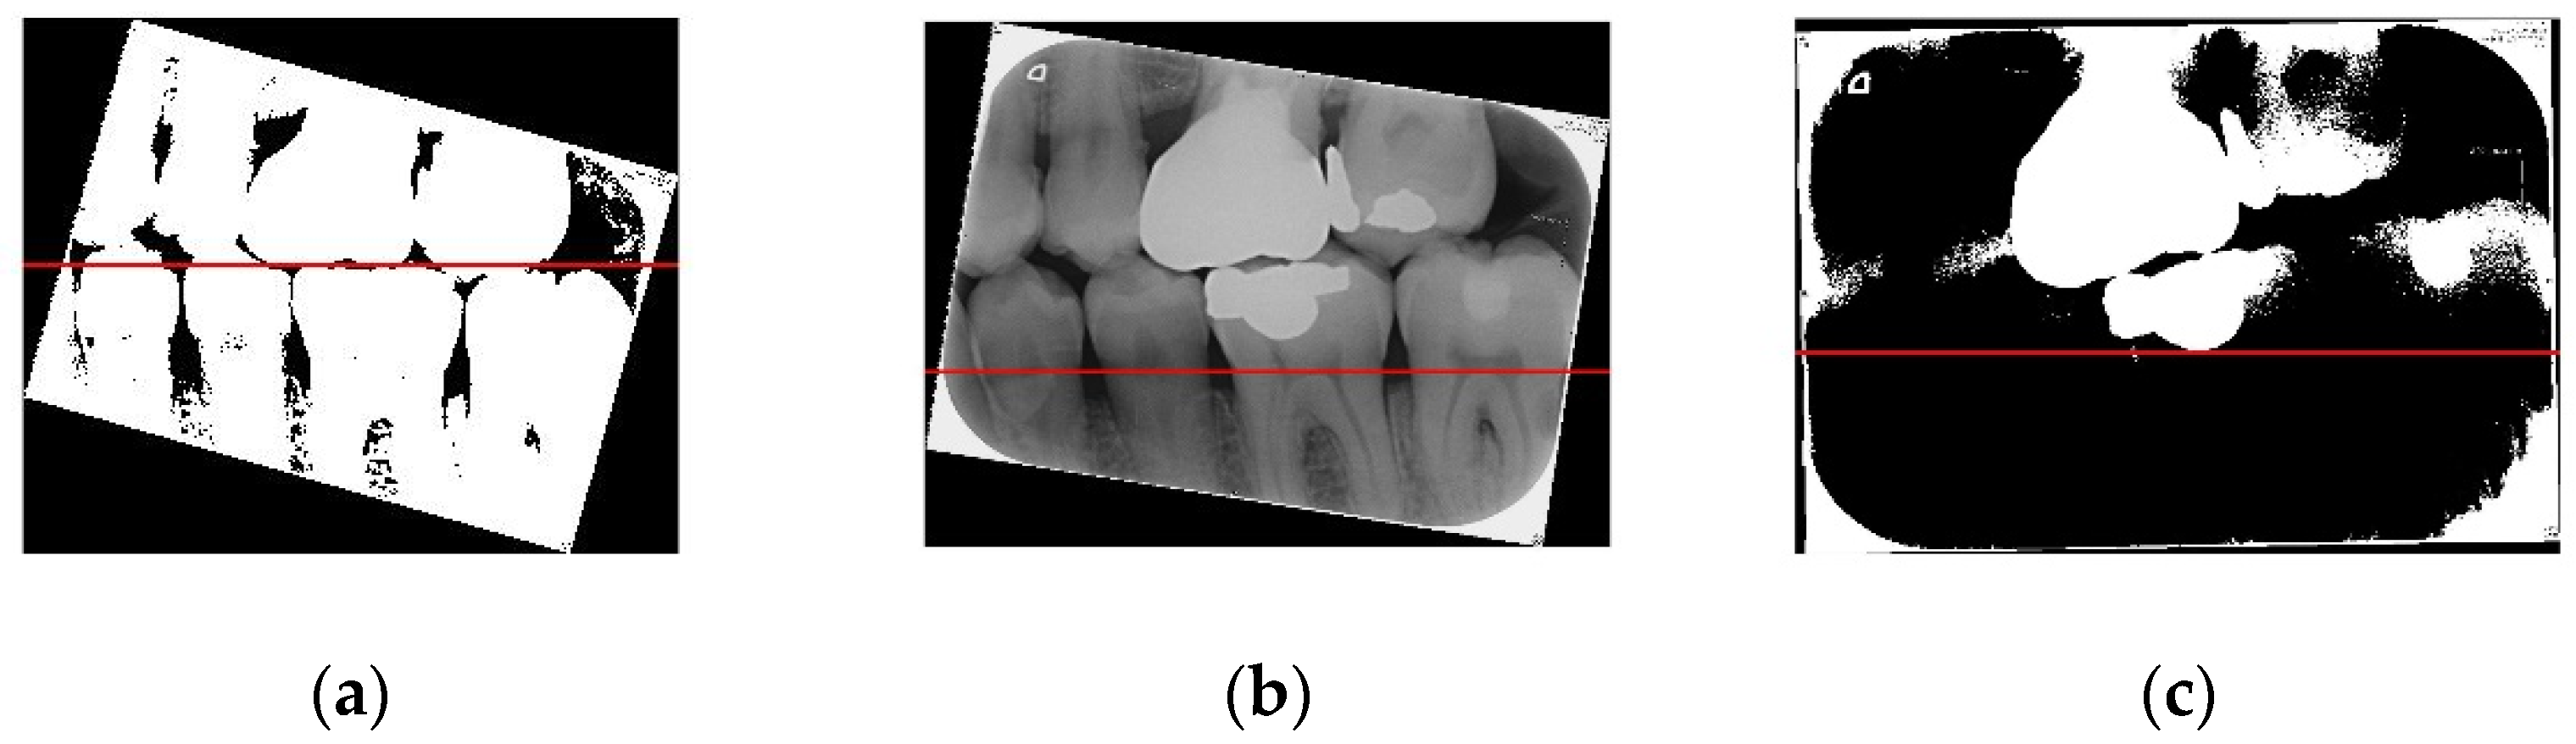

Figure 8 shows the importance of image preprocessing through the Gaussian filter and Otsu’s thresholding for image cropping.

Figure 8.

(a) Image processed through the Gaussian filter and Otsu’s thresholding, where the red line separates the upper and lower teeth; (b) image without any processing, where the red line separating the upper and lower teeth is very imprecise; (c) image processed only through Otsu’s thresholding, where the red line separating the upper and lower teeth is also imprecise.